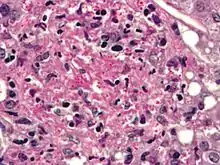

Infecting C. neoformans cells are usually phagocytosed by alveolar macrophages in the lung.[11] The invading C. neoformans cells may be killed by the release of oxidative and nitrosative molecules by these macrophages.[12] However some C. neoformans cells may survive within the macrophages.[11] The ability of the pathogen to survive within the macrophages probably determines latency of the disease, dissemination and resistance to antifungal agents. In order to survive in the hostile intracellular environment of the macrophage, one of the responses of C. neoformans is to upregulate genes employed in responses to oxidative stress.[11]